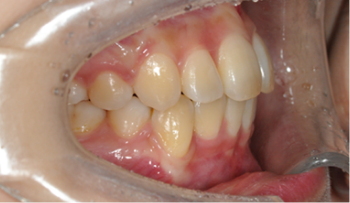

영구 치열의 교정 치료

교정 치료 진료 과정

자료 채득

X-ray, 구강 내ㆍ외 카메라 사진, 치아 모형, 턱관절 및 치주 상태,